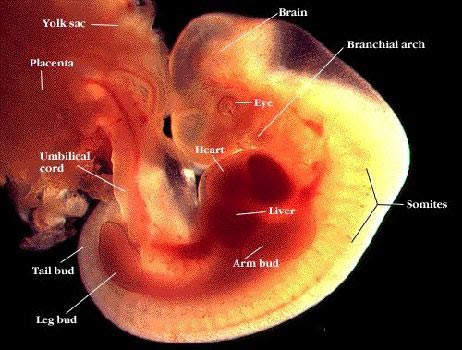

Lo Sviluppo Dell Embrione Feto

7 Settima Settimana Di Gravidanza Periodofertile It

Feto Dalla Settimana 8 Alla 12 Sito Ufficiale Chicco It